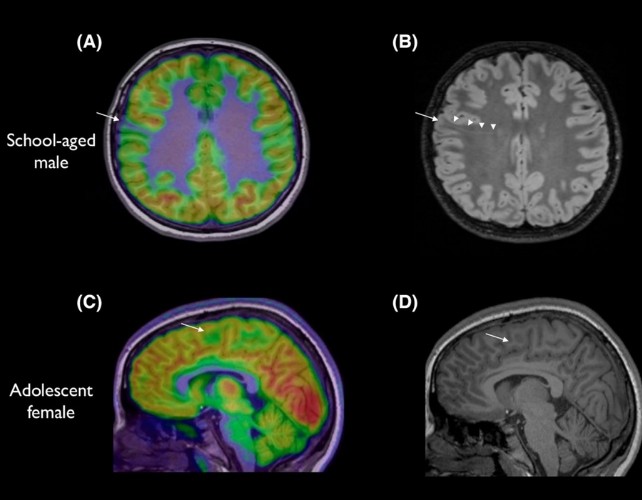

Tiny brain lesions can escape detection on MRI, particularly those tucked at the bottom of a brain fold. In the study, 80% of the children had prior MRI results that were normal, suggesting many surgical candidates were overlooked before artificial intelligence was involved. The scale and subtlety of these abnormalities mean a missed diagnosis can delay life-changing treatment.

Led by paediatric neurologist Emma Macdonald-Laurs at the Royal Children’s Hospital in Melbourne, the team trained an AI tool on pediatric brain images to detect lesions the size of a blueberry or smaller. When the AI analyzed both MRI and PET scans, its performance reached 94% in one test group and 91% in another. Of 17 children in the first group, 12 had surgery to remove their brain lesions, and 11 are now seizure-free. The researchers plan to test the detector in more real-life hospital settings with undiagnosed patients.

Epilepsy affects about one in 200 children, and about a third of cases are drug-resistant. Experts call these results exciting and a strong proof of concept. A related study from King’s College London using AI on MRI data alone spotted 64% of epilepsy-linked brain lesions missed by radiologists. PET imaging can add value, but it is expensive, less widely available, and involves radiation. The AI tool is not meant to replace radiologists or doctors; it acts as a detective to help piece together clues more quickly.